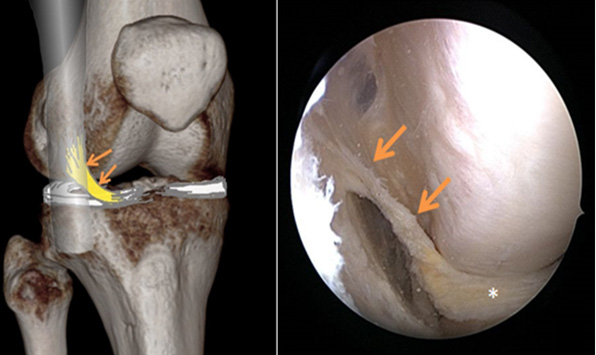

Das Kniegelenk wird sehr häufig mittels MRI untersucht und auch während Operationen regelmässig auf Abnormitäten geprüft. Man meinte bisher, die Anatomie dieses Gelenkes bis ins Detail zu kennen. Das AIML aber war bis heute noch nicht beschrieben worden. Es ist ein schmaler Faserzug, der zwischen dem Tractus iliotibialis (einem Sehnenstrang entlang der Aussenseite des Knies) und dem Aussenmeniskus verläuft.

Das AIML ist laut der soeben veröffentlichten Studie eine anatomische Variante der Aufhängung des Aussenmeniskus. In einer Analyse von MRI-Untersuchungen bei über 1000 Personen war das AIML in 13% der Fälle vorhanden. Die Studie wurde von Forschenden der Orthopädie und Radiologie der Universitätsklinik Balgrist durchgeführt.

Obwohl es sich um eine anatomische Variante handelt, ist das Vorhandensein eines AIML im Kniegelenk klinisch bedeutsam. Menschen mit AIML haben ein deutlich erhöhtes Risiko für Risse des Aussenmeniskus als der Rest der Bevölkerung.